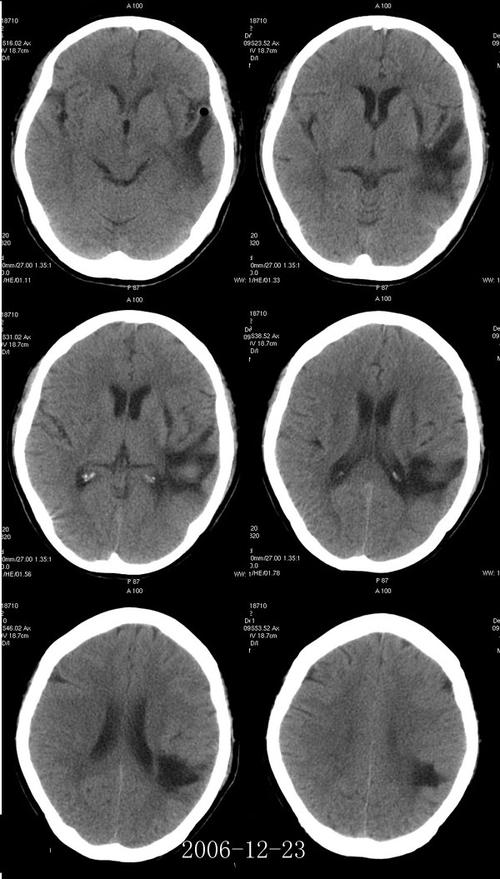

双侧多发腔隙性脑梗赛